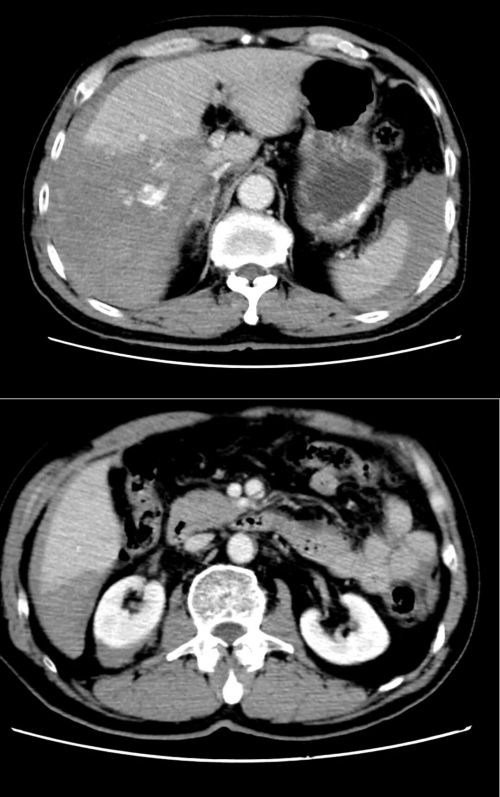

近日,一场惊心动魄的生命救援在衡阳县人民医院与南华大学附属第二医院紧密型医联体协作下圆满完成。一名因意外导致右肝破裂、肾挫伤、多发性肋骨骨折及肺部严重挫伤、一度生命垂危的患者,在两家医疗机构高效协同、多学科专家联合施治下重获新生。

针对患者肝、肾、胸、肺多处严重损伤,专家团队迅速开展多学科会诊(MDT),制定精准手术及治疗方案。在南华二附院肝胆外科吴江主任的指导下,成功实施右肝不规则切除与止血手术,同时行胸腔闭式引流以稳定呼吸功能。